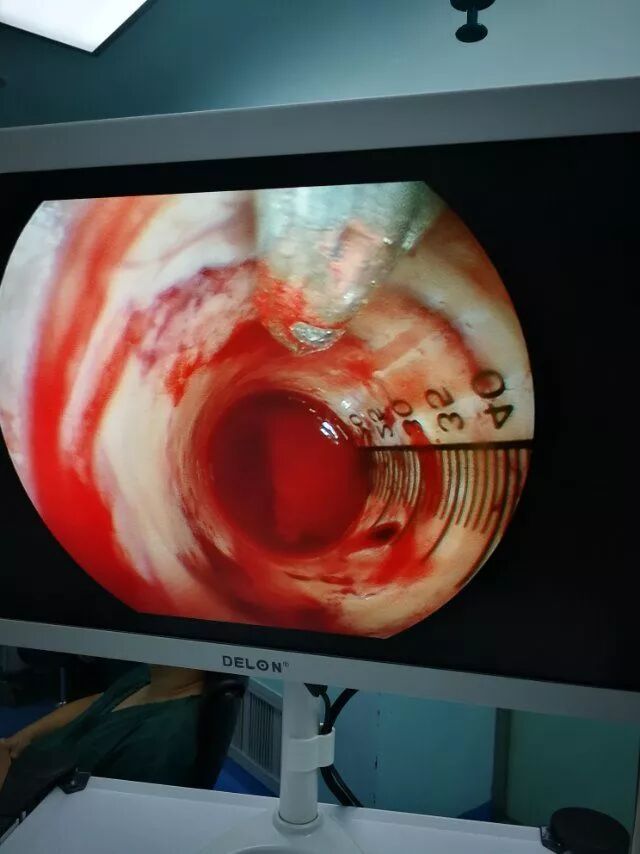

放置套筒(北京301亿元陈晓雷主任专利)

放置到血肿腔

内镜下清血